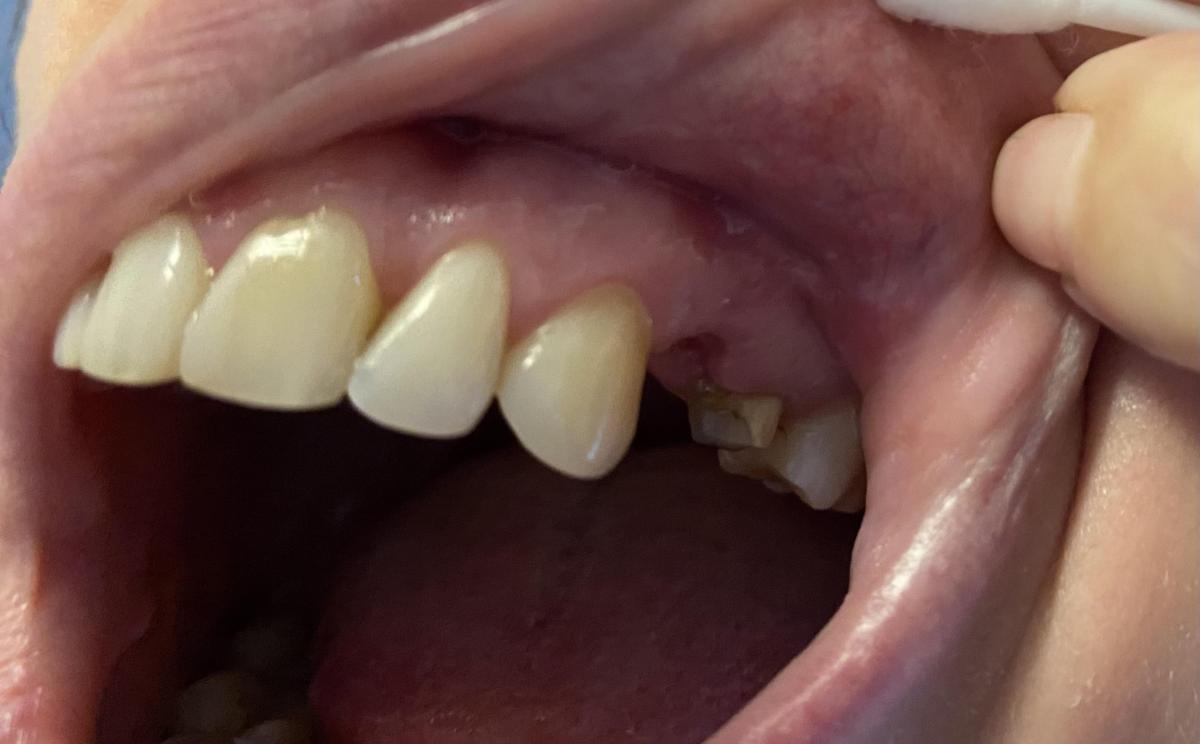

Юрий Жигурт, извините, не сразу получилось прикрепить, только после авторизации. Я просила сделать фото именно этой зоны, где болит.

yuliya--guseva, ещё фото десны сделайте, пожалуйста!?

Юрий Жигурт,

yuliya--guseva, спасибо!

Предполагаю, что что-то осталось!?

Я бы сделал дополнительную чистку...

yuliya--guseva, это зачем? Надо исключить пульпит клыка...